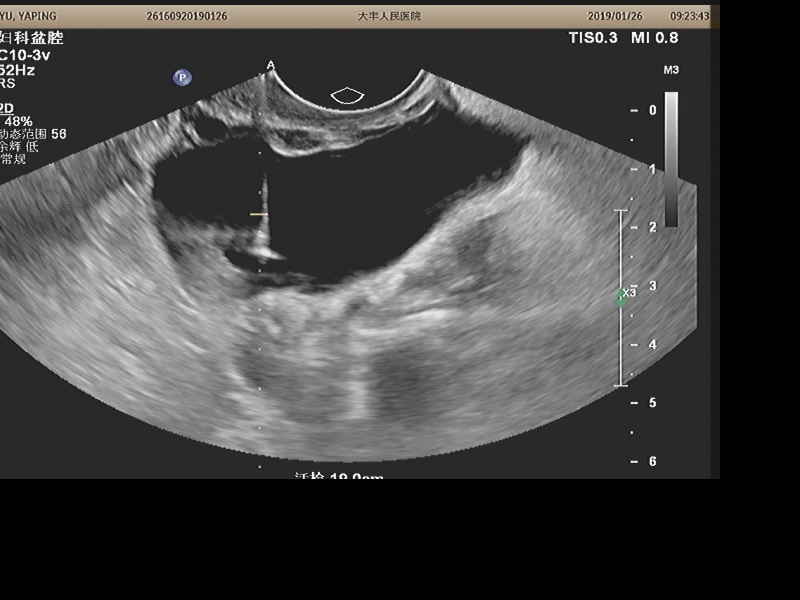

超声监视下将穿刺针刺入囊性病变中心抽吸囊液